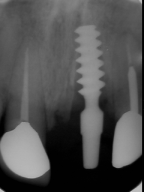

| 抜いた所をよく洗浄してから、 インプラント(人工歯根)を植えます。 |

| インプラント(人工歯根)を植えた所に 仮歯(テック)を作り、手術の終わりです。 骨が固まるまで数ヶ月待ち、それから、 はずした歯(補綴物)が入ればそれを 入れます。 歯の周りにあるのは、ゴムで、血(血餅)が流れ 出ないようにしています。こうする事によって、 きれいな歯ぐきが再生されます。 |